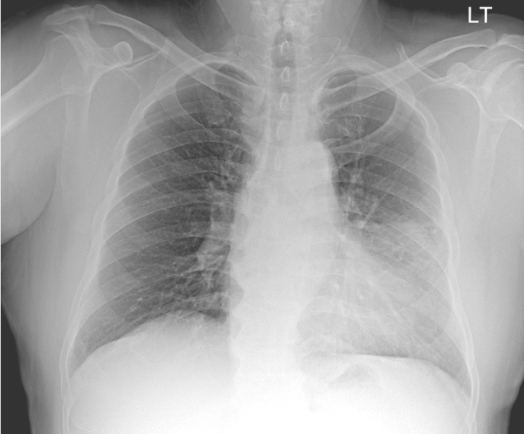

20¼¼³²ÀÚ

³»¿ø 1°³¿ù ÀüºÎÅÍ´Â ÀæÀº ±âħ°ú ÇÔ²² °¡½¿ ´ä´ä°¨, ¾ÈÁ¤

½Ã È£Èí°ï¶õÀÌ µ¿¹Ý,³»¿ø 15ÀÏ Àü, Ÿº´¿ø¿¡¼­ ±â°üÁö¿°, õ½Ä Áø´Ü.

³»¿ø 1³â 6°³¿ù ÀüºÎÅÍ ÇÏ·ç 1°©¾¿ Èí¿¬·Â

¹éÇ÷±¸ 7,330/¥ìL, Ç÷»ö¼Ò 15.4 g/dL